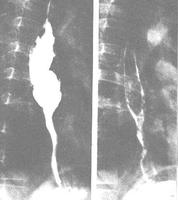

X線鋇劑造影症狀可在術後數日至數年出現,表現為中上腹持續性或無規律性燒灼痛,進食後稍加重,服抗酸劑無效。15%~25%噯出膽汁或有膽汁性嘔吐,嘔吐後症狀無明顯緩解,嘔吐常於早晨清醒時發生。X線鋇劑造影檢查不能確定診斷。由於胃黏膜糜爛引起失血,可致術後低色素性貧血。

膽汁手術後反流性胃炎應與輸入袢綜合徵鑑別,後者是因輸入袢近吻合口處的間歇性梗阻造成,二者有相似之處,但治療不同。輸入袢綜合徵表現為進食後即感陣發性上腹痛、腹脹,常有膽汁性嘔吐,但嘔吐後症狀即緩解,由於食物在嘔吐前已進入輸出袢,故嘔吐物中無食物。X線鋇劑造影檢查可確定診斷。